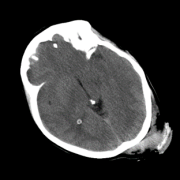

So far we have observed enhanced performance through the SA term. In this subsection, we visually illustrate how this novel term imposes smoothness between attention scores of consecutive slices, leading to more accurate predictions. Figure 2 shows plots of the attention scores assigned by SA-DMIL- and Att-MIL to the slices of three different scans (Fig. S1 in the appendix contains an analogous plot for SA-DMIL-). As expected, introducing the SA loss results in smoother attention weights. Note that the smoothness constraint of SA-DMIL effectively penalizes the appearance of isolated non-smooth attention weights that incorrectly jump over or below the threshold.

We also include visual examples of consecutive CT slices in Fig. 3. In Scan 1, the baseline Att-MIL produces a wrong prediction at scan level. When using SA, the prediction is correct since dependencies between adjacent slices have been learned. In Scan 2, both models produce correct predictions at scan level, but SA-DMIL is more accurate at slice level. This occurs thanks to the SA loss, that turns the attention scores into smoother values and, therefore, avoids random jumps up and down the decision threshold.